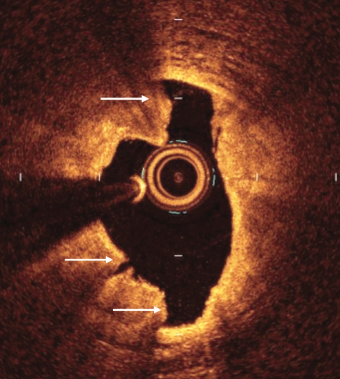

Quiz: When to Use IVL: An Exploration of Treatment Algorithms

This quiz is based on an interview with Evan Shlofmitz, DO. Click here to read "When to Use IVL: An Exploration of Treatment Algorithms".